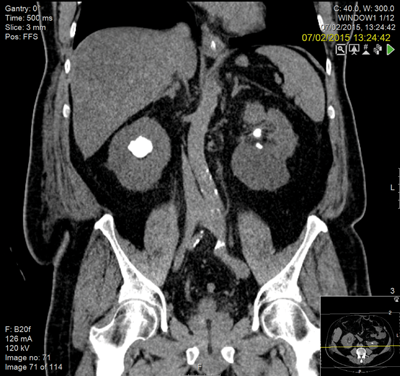

A general practitioner ultrasound was performed on a 29-year-old woman which hinted at bilateral stones. She gave a history of urinary tract infections throughout her pregnancy but had no paediatric history of note. She weighed 105kg with a body mass index (BMI) of 43 and was chronically anaemic with a haemoglobin of 97 and a creatinine of 186 and urine colonised with E. coli.

Following discussion at an X-ray meeting and a nephrology opinion, a left-sided percutaneous nephrolithotomy (PCNL) was performed in the prone position. Two tracts were placed by the urologist into the mid and upper portion of the kidney, clearing a reasonable volume and the patient was left with two nephrostomy tubes. The patient developed a postoperative reactive pleural effusion and chest infection requiring a chest drain. A prone CT revealed no radiological evidence of a pleural injury.

The lower pole is my concern. She has a degree of infundibular stenosis exiting the upper pole and indeed entering the lower pole, with poly-calyceal disease. She already has cortical thinning and will require many percutaneous punctures to clear her of stones on the left side. At the end of this, of course, she may be left with very little residual function. We are then faced with the right kidney. I requested a second opinion from a London teaching hospital and no change in management was suggested.